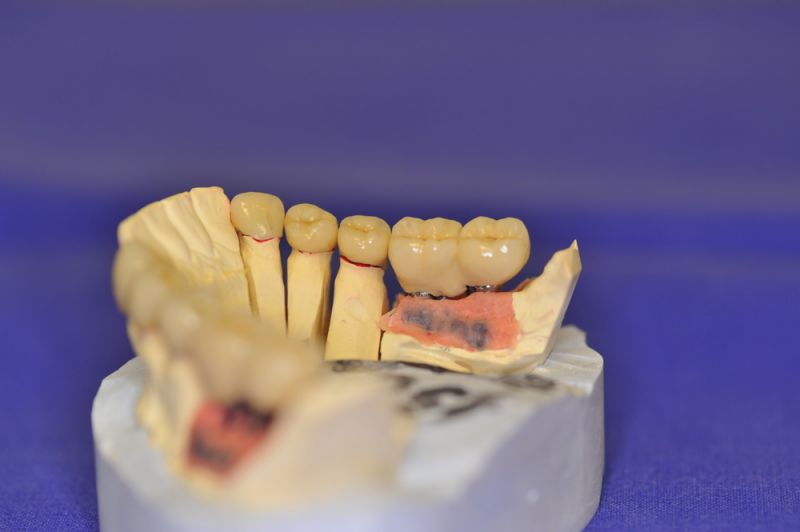

Mit dem heutigen Tag geht eine der technisch schwierigsten und anspruchsvollsten Arbeiten zu Ende, die im CMD-CENTRUM-KIEL jemals erstellt worden ist. Dabei sind es nur 10 Kronen, die benötigt werden, um die starken Kopf- und Gesichtsschmerzen der Patienten zu beseitigen.

1. Notwendigkeit einer implantatgestützten Kronenversorgung mit der Vorgeschichte, dass die Patientin eine Vielzahl von Behandlern aufgesucht hatte, die eine Implantation im Unterkiefer als nicht durchführbar einschätzten.

2. Extrem schlechte knöcherne Verhältnisse im Unterkieferseitenzahnbereich, die sich intraoperativ noch einmal als ungünstiger darstellten, als bereits in den Voruntersuchungen erkennbar.

3. Sehr dünne Implantate, die von ursprünglich zwei je Kieferhälfte auf letztendlich drei je Kieferhälfte umgeplant werden mussten.

4. Notwendigkeit die Mundhygienefähigkeit der Arbeit auch unter sehr beengten Verhältnissen zu schaffen, um der Arbeit eine günstige Prognose mitzugeben.